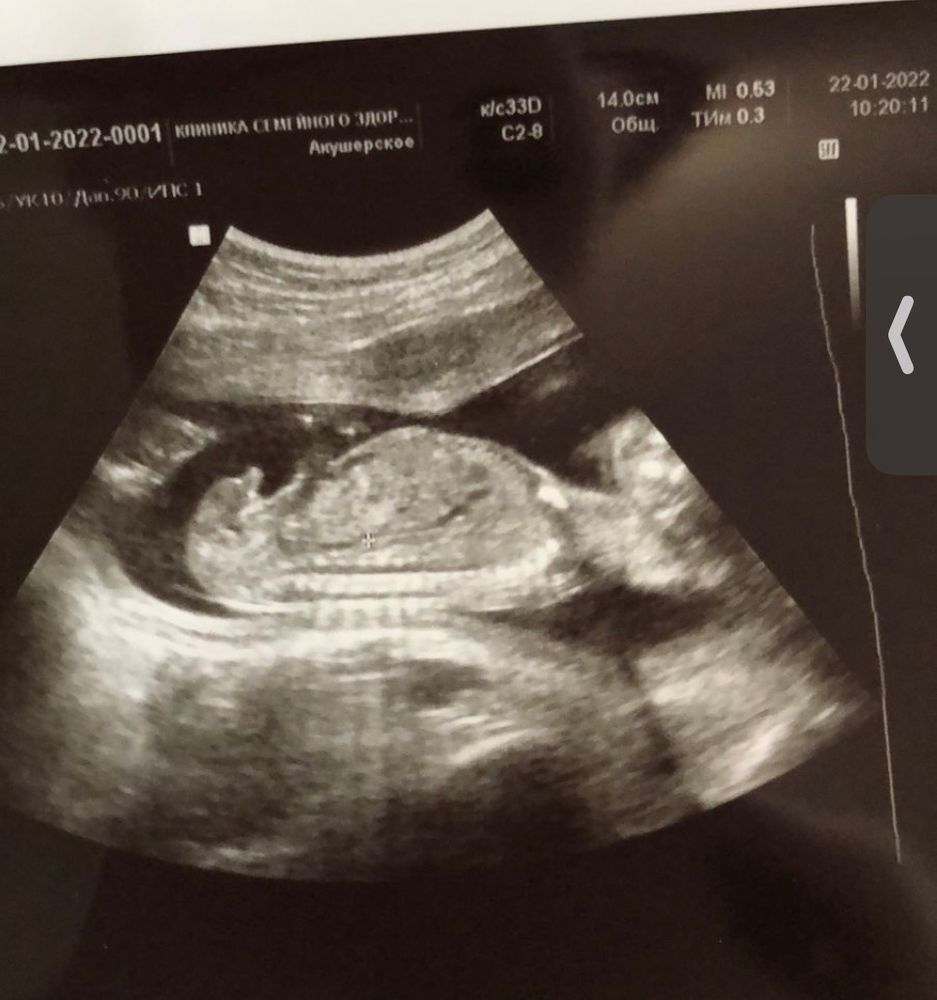

Виктория, первую фотку не нашла , но нашла на 15 недели или 18 точно не помню Изображение